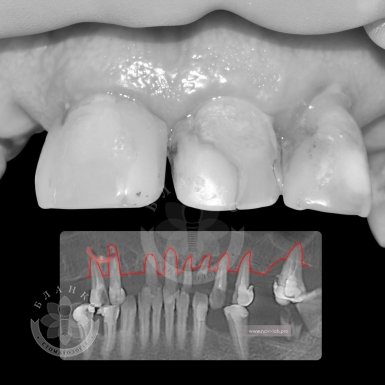

- Consultation with a specialist. The doctor will conduct diagnostics, including a 3D image of the jaw to assess the condition of the bone tissue.

Installation of six implants "turnkey" is a comprehensive dental service that includes all stages of treatment, from diagnostics to installation of a fixed structure. In the complete absence of teeth in the jaw (edentia),six implants are distributed in certain areas to evenly distribute the load.

The procedure usually consists of several stages: diagnostics, treatment planning, installation of implants and subsequent fixation of a fixed prosthesis.